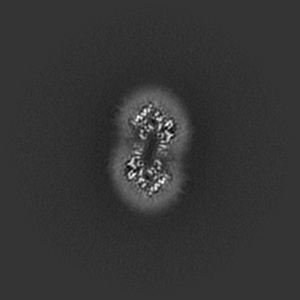

Cryo-EM structure of human Anion Exchanger 1 bound to Dipyridamole

Single-particle3.13 Å

Sample: Dimeric anion exchanger 1 (SLC4A1)